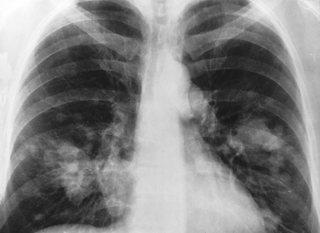

poumons-radio-cancer-amiante-web